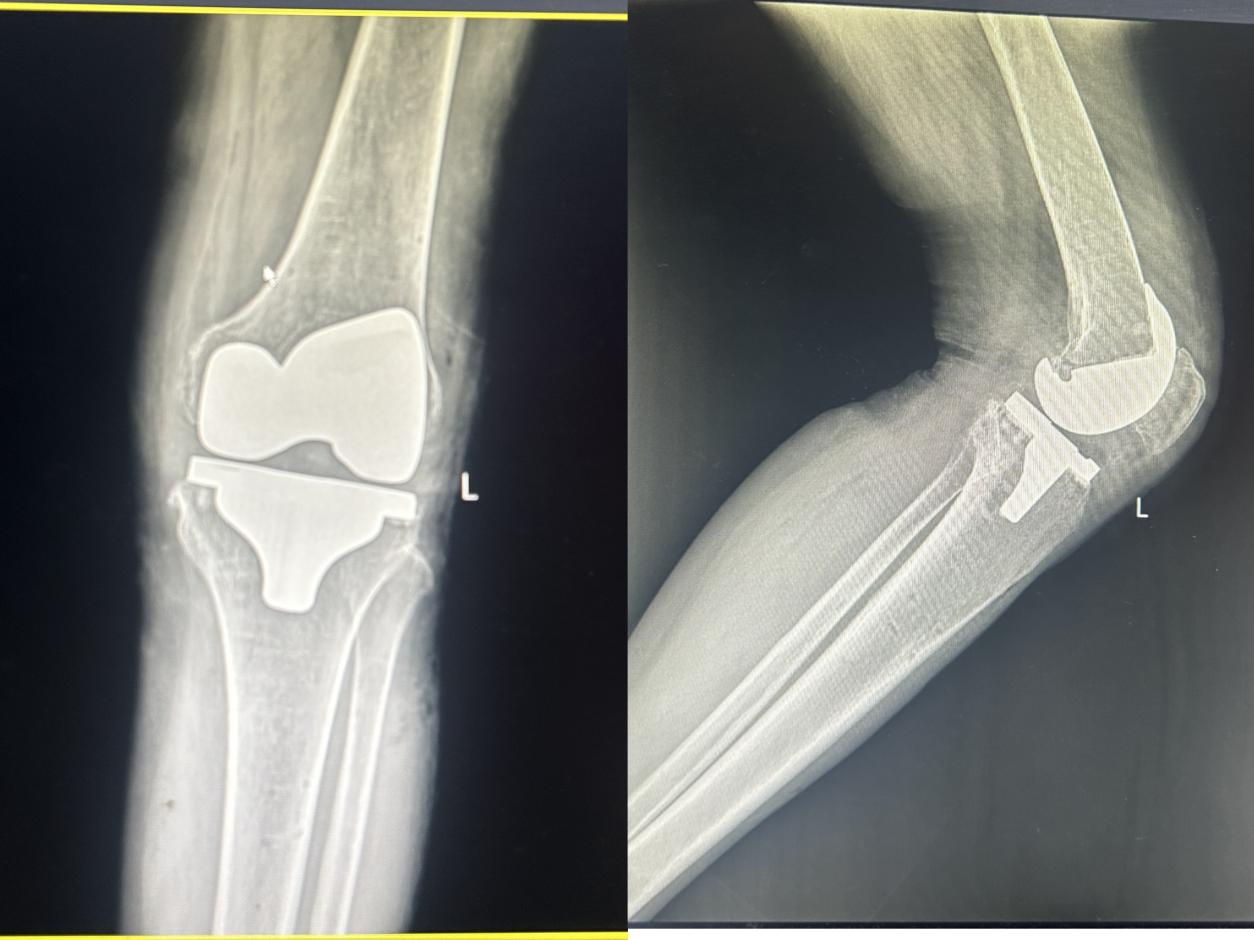

一位长期受膝关节疼痛困扰的中年女性,日常无法正常生活。经过王坤正教授、杨佩教授团队详细的检查和诊断,确定该患者需要进行膝关节置换术以缓解疼痛并恢复关节功能。在手术过程中,我们采用了先进的MAKO机器人辅助技术。首先,通过CT扫描获取患者的膝关节三维数据,为机器人提供精确的骨骼模型。随后,医生在机器人的辅助下,制定了个性化的手术方案,并精确控制了手术过程中的截骨和假体植入等操作。手术过程顺利,术后患者疼痛明显减轻,关节功能得到显著改善。经过一段时间的康复锻炼,患者已经能够正常行走,生活质量得到了极大的提升。